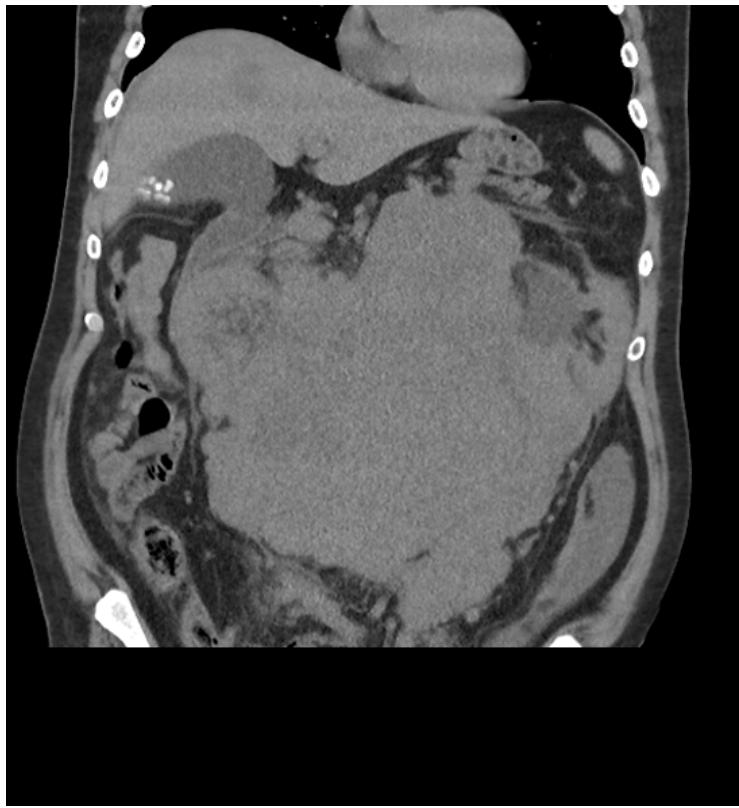

The abdominal and pelvic CT in Figure 1 and Figure 2 revealed a large undifferentiated mass localized throughout the abdomen and pelvis (transverse dimensions: $25.4 \times 22.8$ cm). The CT scan in Figure 1 also demonstrated left kidney displacement and encasement of the abdominal aorta, visceral branches, and inferior vena cava. There is also encasement of the small and large bowel loops in the upper abdomen and this mass extends into the central pelvis. The liver in Figure 2 also highlights one of the many multiple solid lesions spread throughout both hepatic lobes and is mainly right-sided. The largest solid lesions in segment 6 and 4A are respectively measuring up to $3.2$ cm and $2.9$ cm. Our patient proceeded to have further staging scans which did not reveal any metastatic depositions to the chest, head, and neck.

Figure 2: Coronal slice of the abdomen noting same mass with significant displacement of the bowels. A hypodense lesion can be visualised on the liver